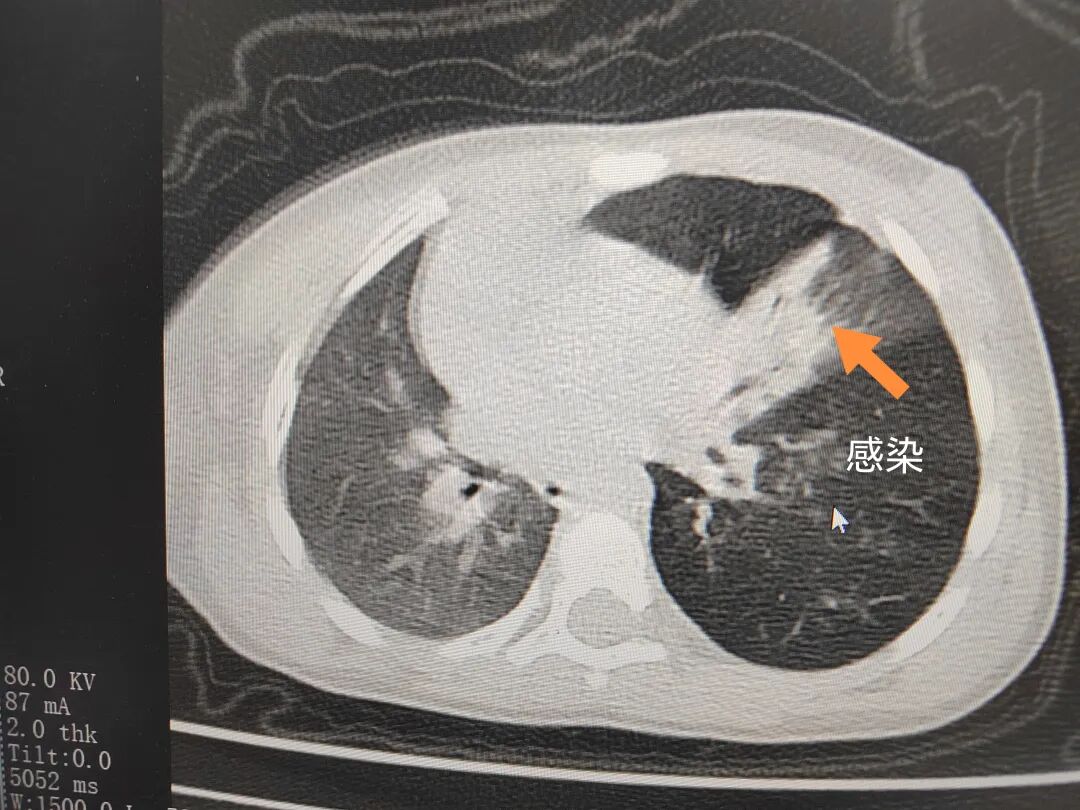

三天后(11月13日),趙寶出現(xiàn)高熱、咳喘加重,家長著急了,再次帶他來到醫(yī)院。CT檢查顯示左肺過度充氣,左肺上下葉支氣管主干見不規(guī)則高密度影,左肺上葉可見大片狀密度增高影,縱隔窗實(shí)變,提示為“左側(cè)支氣管內(nèi)異物并繼發(fā)性改變,左肺上葉舌段肺膨脹不全”。

市二院小兒呼吸內(nèi)科團(tuán)隊(duì)迅速為患兒制定了周密的手術(shù)方案,并很快安排了氣管鏡探查。術(shù)中,主治醫(yī)師田慧等憑借嫻熟的氣管鏡操作技術(shù)成功將異物大塊板栗取出。由于板栗在氣管內(nèi)存留時(shí)間較長,質(zhì)地軟糯易碎,大大增加了手術(shù)難度。檢查還發(fā)現(xiàn),異物停留部位的氣管黏膜已出現(xiàn)充血紅腫、糜爛,導(dǎo)致患兒住院時(shí)間相應(yīng)延長。此次事件給趙寶的家庭帶來了不小的驚嚇與擔(dān)憂,也再次為廣大家長敲響了警鐘。

市二院小兒呼吸內(nèi)科副主任楊亞娟介紹,異物誤入氣道可能導(dǎo)致氣道阻塞,嚴(yán)重時(shí)可引發(fā)窒息,甚至危及生命。若異物進(jìn)入支氣管,造成不完全堵塞,可引起阻塞性肺氣腫;如完全堵塞支氣管,則可能導(dǎo)致肺組織萎縮,形成肺不張。此外,若異物存留時(shí)間較長,或?yàn)橹参镄援愇铮菀缀喜⒓?xì)菌感染,產(chǎn)生膿性分泌物,進(jìn)而發(fā)展為肺炎。她強(qiáng)調(diào),盡早診斷并取出異物,是減少并發(fā)癥、降低病死率的關(guān)鍵。